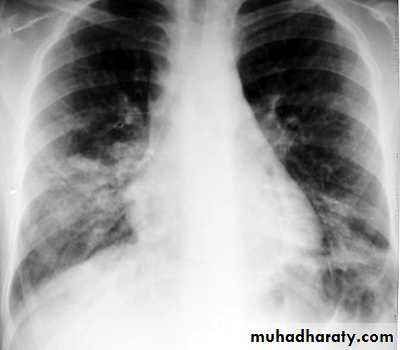

CXR: interstitial or bronchopneumonic, involve mainly the lower lobes. Bilateral diffuse infiltrates, lobar pneumonia or hilar lymphadenopathy can occur in up to 30% . Pleural effusions may occur.

ESR is often elevated.Lower lobe pn